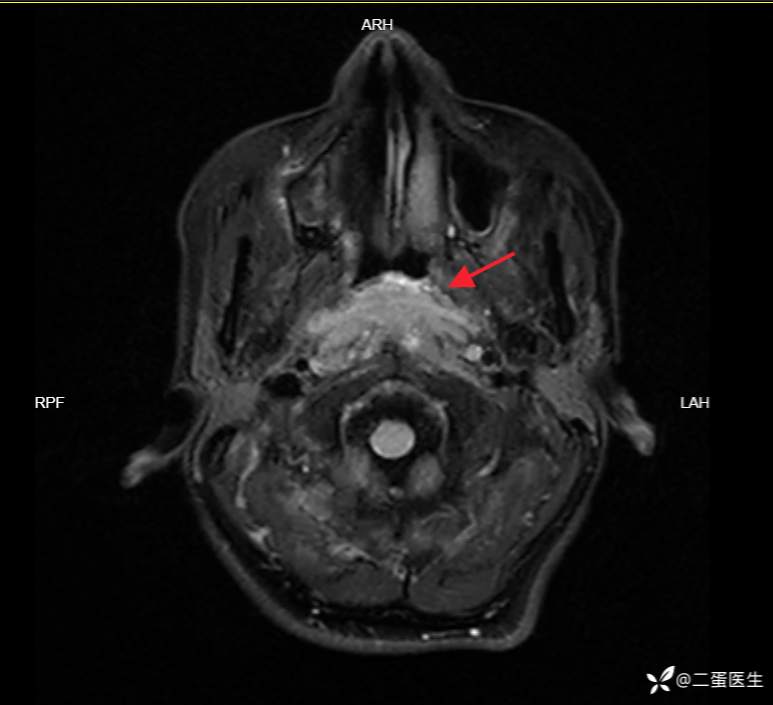

头颅CT见“鼻咽部软组织增厚明显”,进一步完善头颅增强MRI,提示“鼻咽腔软组织填充、强化,两侧头长肌及两侧翼内肌信号改变”。